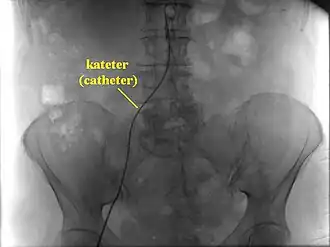

Непосредственно при исследовании пациент укладывается на ангиографический стол, фиксируется и подключается к кардиомонитору, в вену устанавливается катетер для инъекций. Перед исследованием через катетер проводится премедикация: введение антигистаминных препаратов (профилактика аллергических реакций), транквилизаторов, анальгетиков. Исследование проводится путём пункции (прокола) сосуда с последующей катетеризацией (введением в сосуд специального катетера, через который затем будет вводиться контрастное вещество (препарат йода). Чаще всего проводят катетеризацию бедренной артерии. Все действия внутри сосуда осуществляются под контролем рентгенотелевидения. По окончании исследования на область пункции на сутки накладывают давящую повязку.